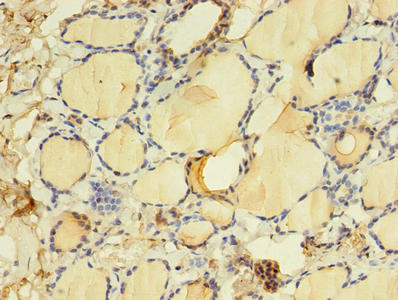

Immunohistochemistry of paraffin-embedded human thyroid tissue using CSB-PA023514LA01HU at dilution of 1:100

Immunohistochemistry of paraffin-embedded human lung cancer using CSB-PA023514LA01HU at dilution of 1:100